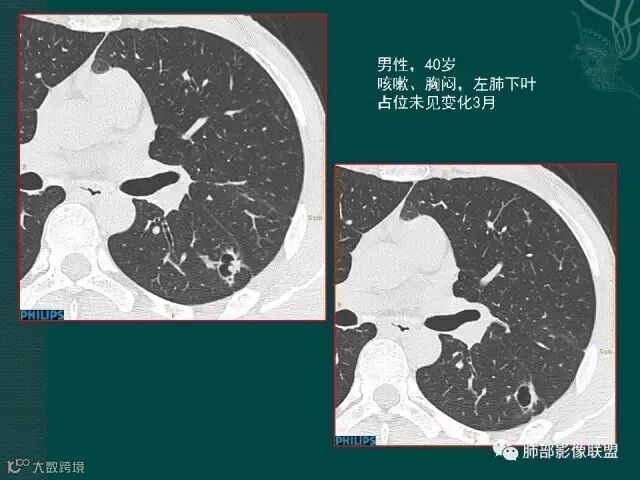

病史似乎是炎性;空洞型病变,靠近纵隔的时候,一定要看对纵隔是否有侵蚀,这是相当重要的。

红箭头所指是右上肺静脉,起始部是完好的,上一层被病变完全包埋,管腔变窄,管壁形态不规则,并侵犯相邻纵隔。

肺癌靠近纵隔时,对纵隔的侵犯,对诊断有重要诊断价值,炎症的话很少会侵犯血管。